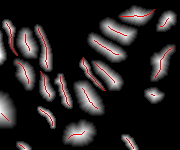

Histopathology image synthesis aims to address the data shortage issue in training deep learning approaches for accurate cancer detection. However, existing methods struggle to produce realistic images that have accurate nuclei boundaries and less artifacts, which limits the application in downstream tasks. To address the challenges, we propose a novel approach that enhances the quality of synthetic images by using nuclei topology and contour regularization. The proposed approach uses the skeleton map of nuclei to integrate nuclei topology and separate touching nuclei. In the loss function, we propose two new contour regularization terms that enhance the contrast between contour and non-contour pixels and increase the similarity between contour pixels. We evaluate the proposed approach on the two datasets using image quality metrics and a downstream task (nuclei segmentation). The proposed approach outperforms Sharp-GAN in all four image quality metrics on two datasets. By integrating 6k synthetic images from the proposed approach into training, a nuclei segmentation model achieves the state-of-the-art segmentation performance on TNBC dataset and its detection quality (DQ), segmentation quality (SQ), panoptic quality (PQ), and aggregated Jaccard index (AJI) is 0.855, 0.863, 0.691, and 0.683, respectively.